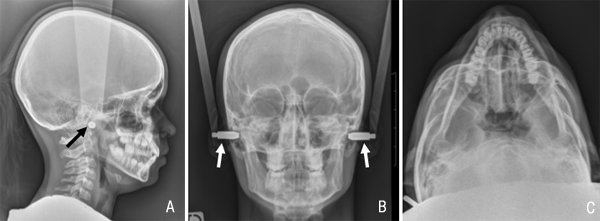

TELERADIOGRAPHIES

C’est un examen qui permet de visualiser, en rapport 1/1 (1cm sur le film = 1 cm sur le corps), la tête dans son ensemble en superposant sur un seul film les contours osseux, les dents et les parties molles du visage.

Il est possible de réaliser plusieurs incidences:

a) de profil. C’est l’incidence la plus fréquente.

b) de face,

c) en incidence de Hirtz.

On positionne des embouts métalliques () dans les oreilles afin de nous permettre de vous mettre dans la position souhaitée et de vous aider à la garder et à ne pas bouger.

Cet examen est fait le plus souvent chez l’enfant dans les bilans d’orthodontie.

Il peut être fait également chez l’adulte dans la même indication.

Bilan préchirurgical pour rétrognatisme. La mandibule est en situation trop postérieure par rapport au maxillaire supérieur.